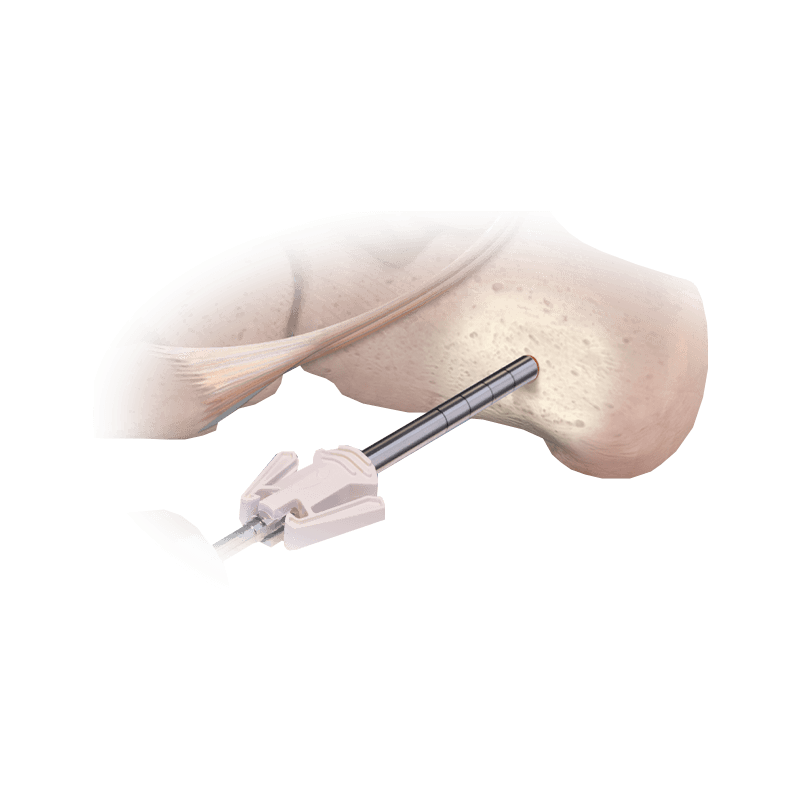

Instruments

ClearGuard LE® Endoscopic Soft Tissue Release System

Disposable instrumentation for a single-portal endoscopic release of the transverse carpal ligament

CoLink® Bone Graft Harvester

A minimally invasive way to morselize cancellous bone from various sites